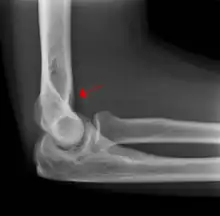

Fat pad sign: Ventral fat pad bowed and dorsal fat pad visible in a case of a nondisplaced fracture of the radius head which is not visible directly.